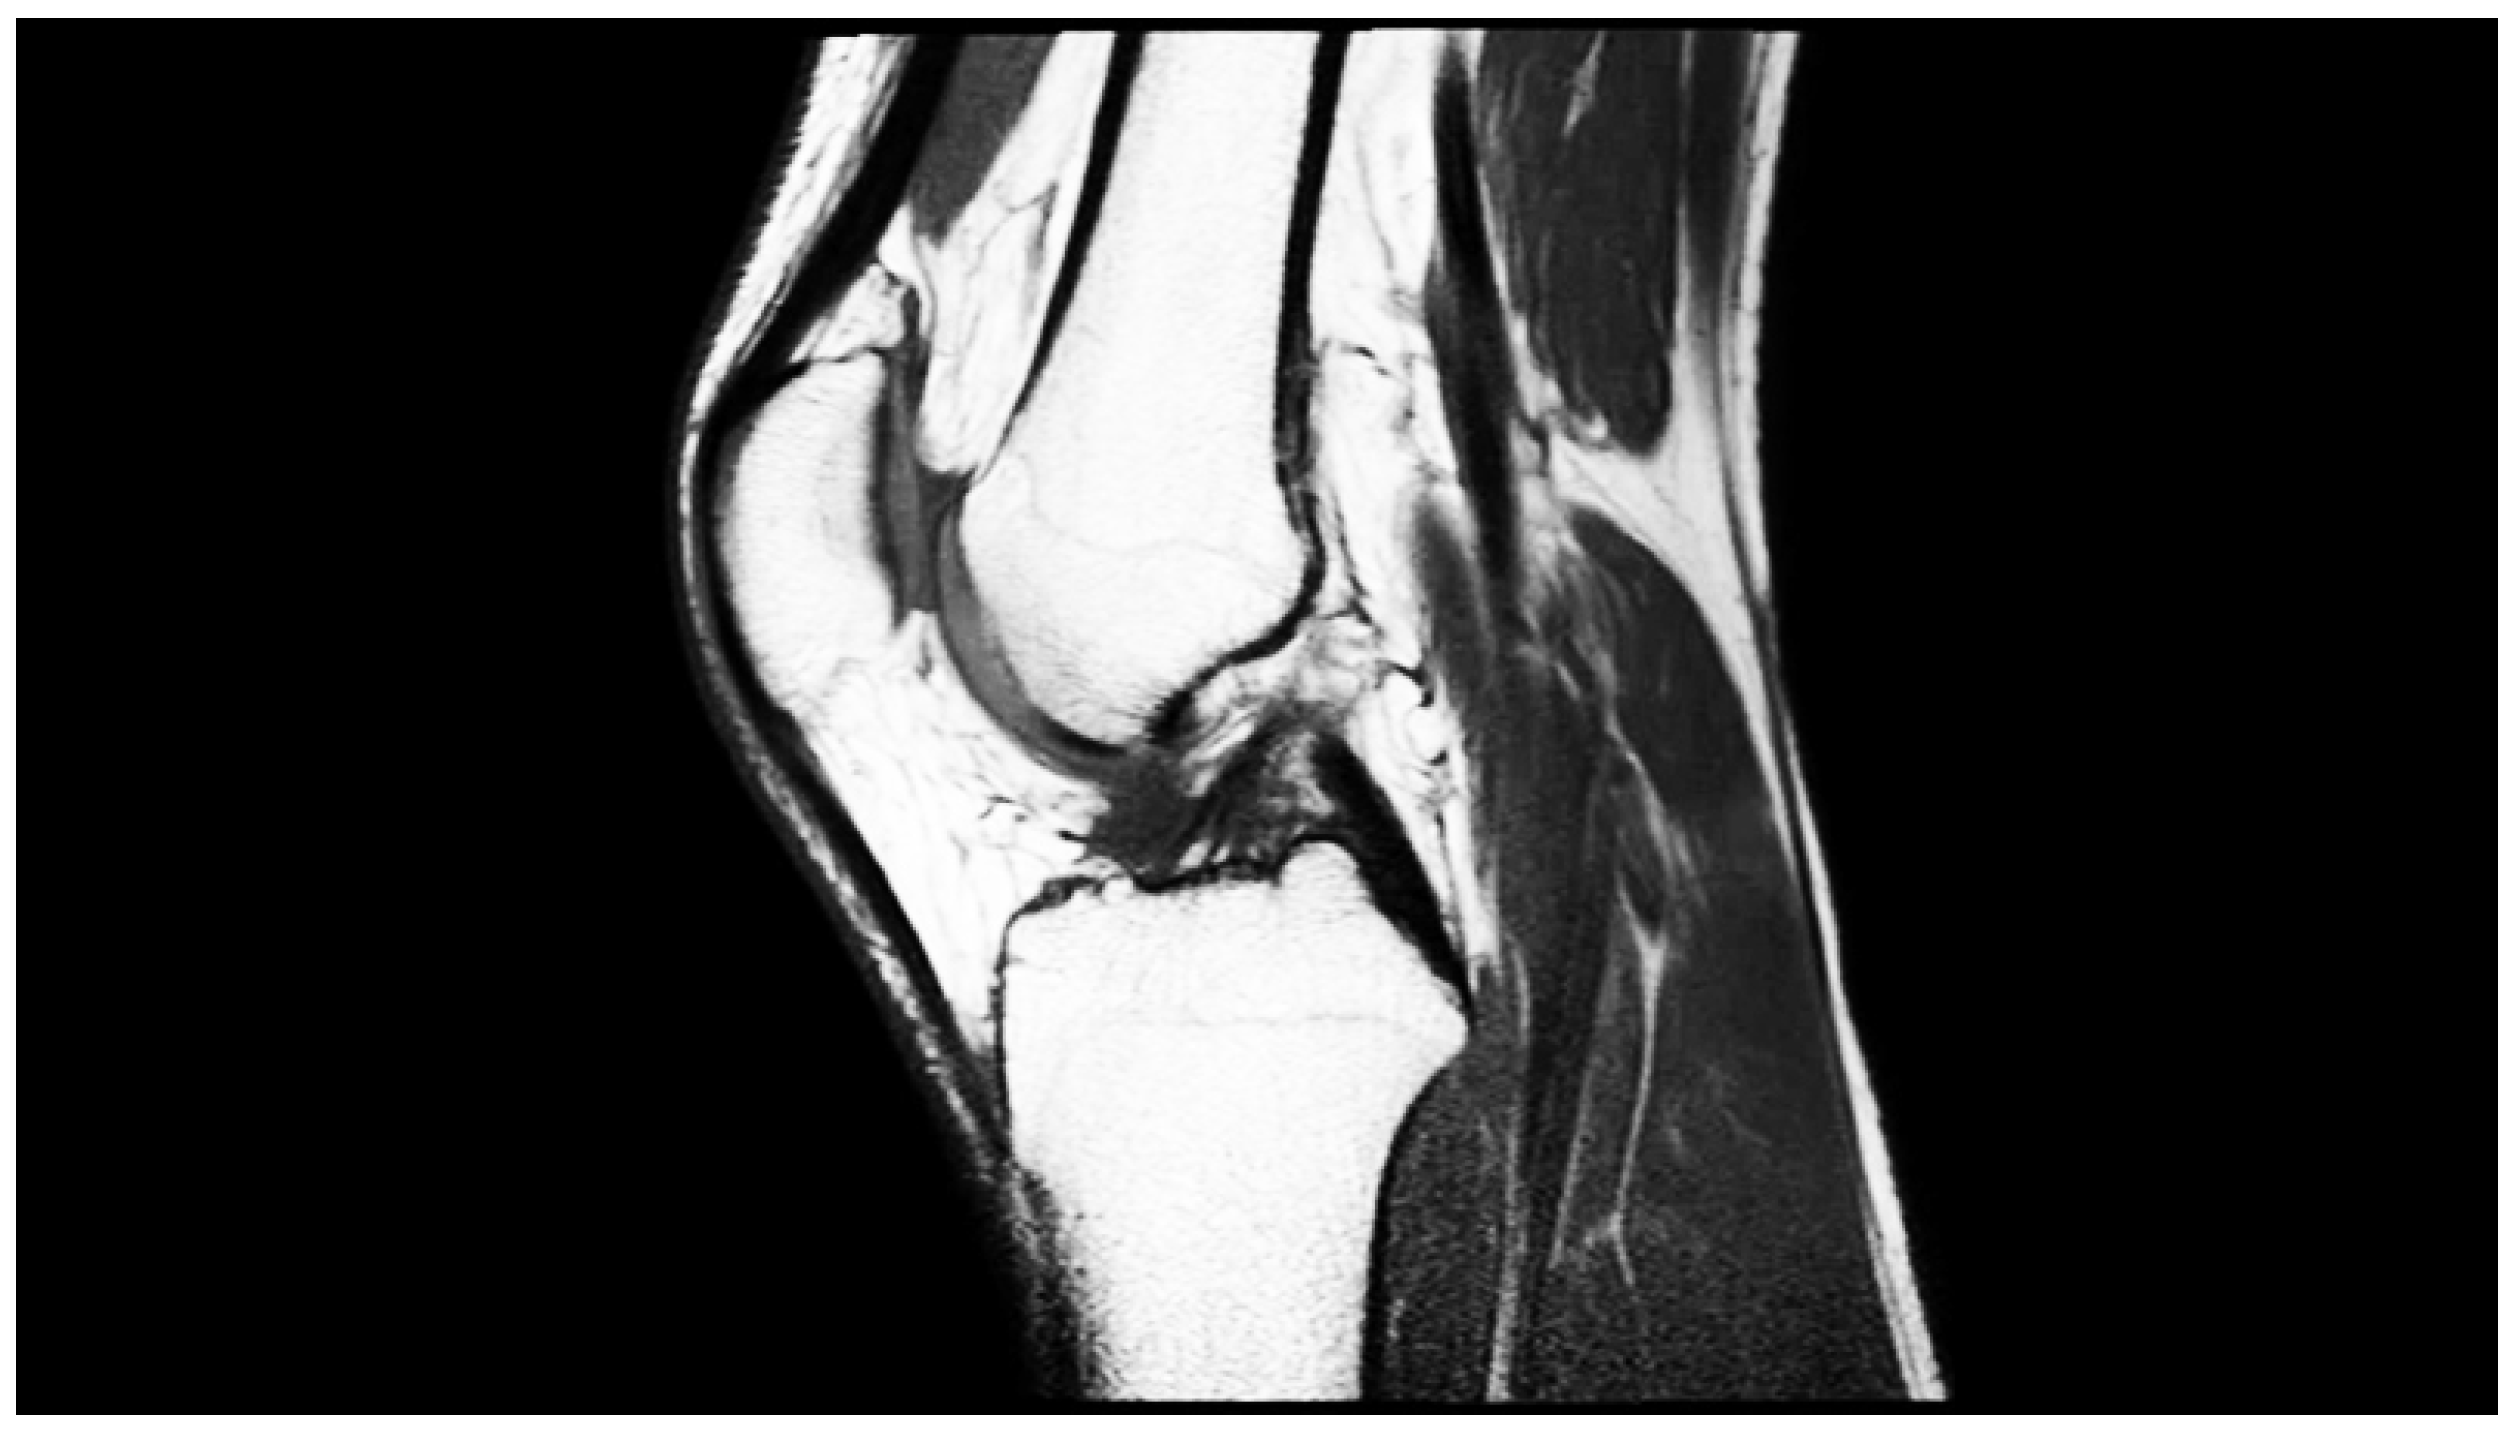

Table 1 represents the running time for three images from well-known image dataset [11] (Figure 1, Figure 2 and Figure 3).

Figure 3. Sagittal MRI image of the knee. Parameters 802 × 450, 8 bits.